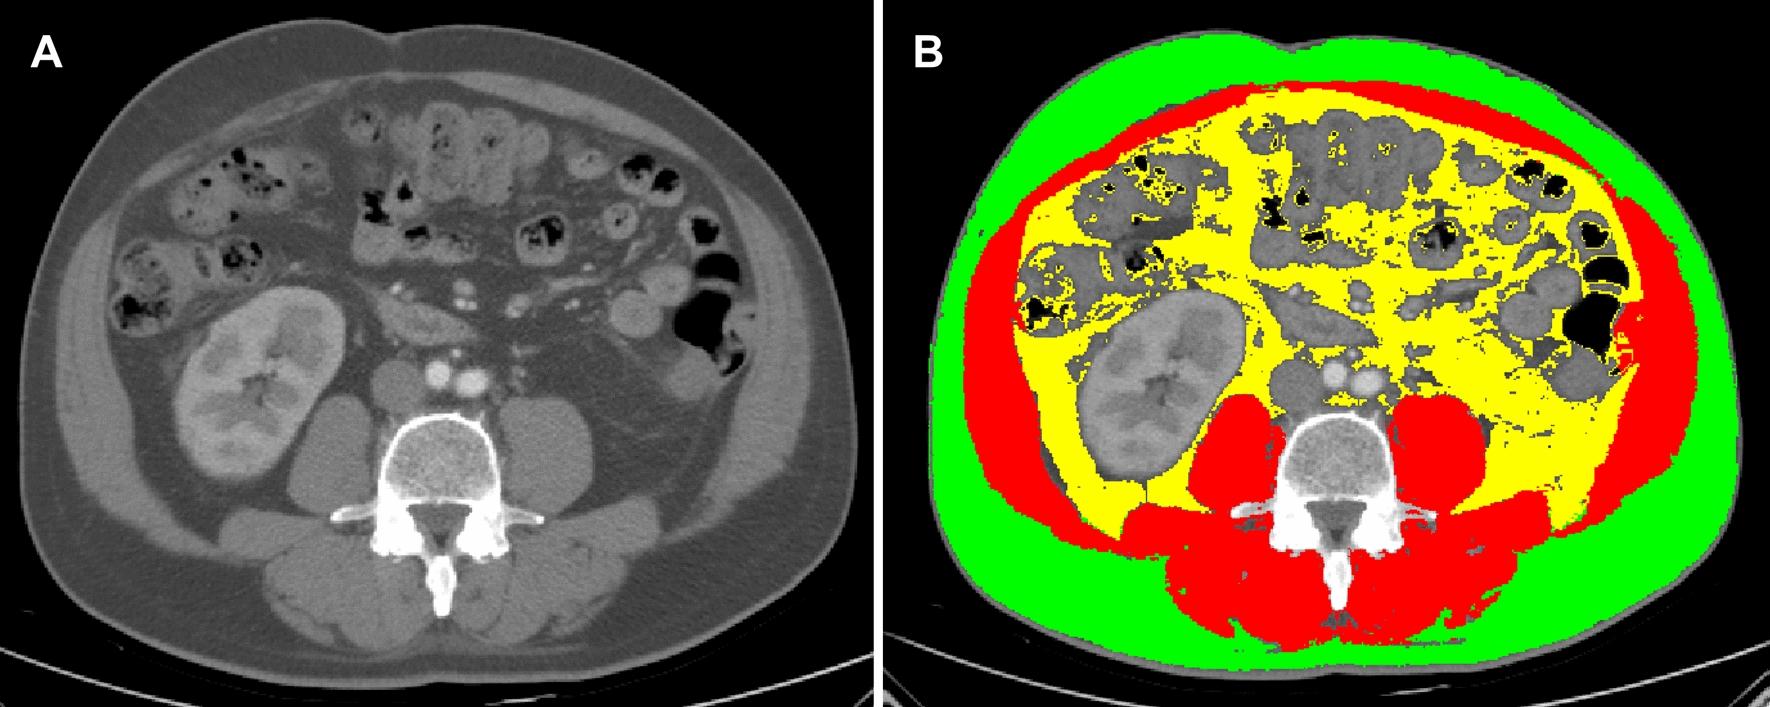

METHODS

This retrospective study evaluated the data of patients who received ICI therapy between June 2019 and August 2023. Automatic segmentation of skeletal muscle, subcutaneous fat, and visceral fat was performed using Slice-O-Matic software, and the corresponding skeletal muscle index (SMI), subcutaneous fat index (SFI) and visceral fat index (VFI) were calculated. The neutrophil-to-lymphocyte ratio (NLR) was determined by dividing the neutrophil count by the lymphocyte count. Univariate and multivariate Cox regression analyses were used to evaluate the correlation between body mass index (BMI), body composition parameters, and the NLR with overall survival (OS) and progression-free survival (PFS) in obese patients receiving ICI therapy.

方法

这项回顾性研究评估了2019年6月至2023年8月期间接受ICI治疗的患者数据。使用Slice - O - Matic软件对骨骼肌、皮下脂肪和内脏脂肪进行自动分割,并计算相应的骨骼肌指数(SMI)、皮下脂肪指数(SFI)和内脏脂肪指数(VFI)。中性粒细胞与淋巴细胞比值(NLR)通过中性粒细胞计数除以淋巴细胞计数来确定。单因素和多因素Cox回归分析用于评估体重指数(BMI)、身体成分参数和NLR与接受ICI治疗的肥胖患者的总生存期(OS)和无进展生存期(PFS)之间的相关性。